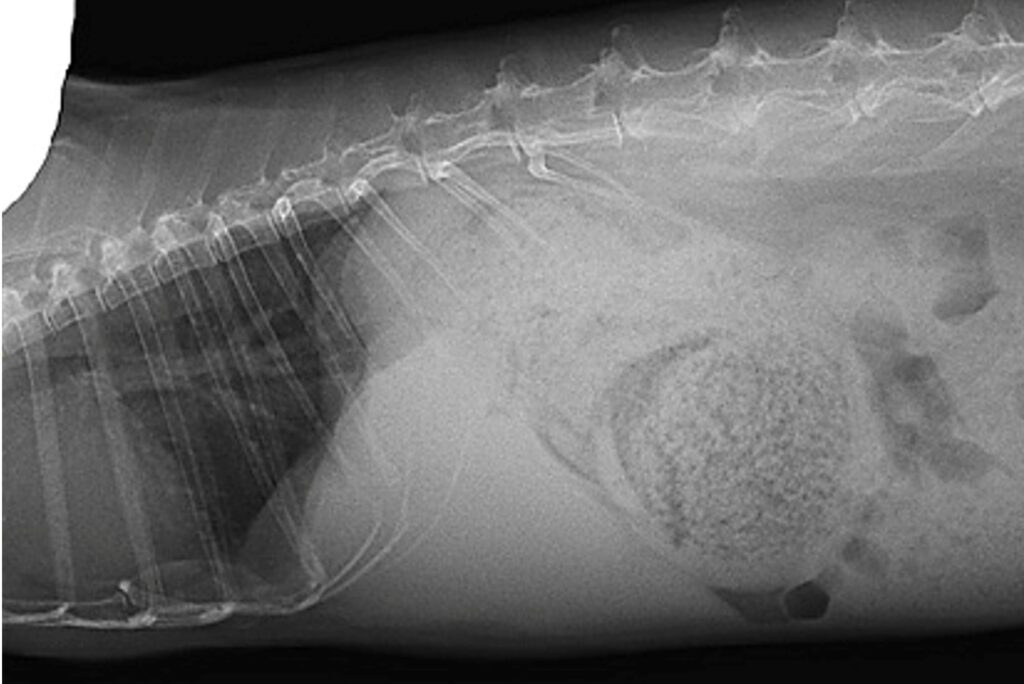

X線検査

X線検査は、腹部全体の概観を得るための一次スクリーニングとして実施されます。肝臓の内部構造を評価することはできませんが、肝臓のサイズ、形状、位置の変化、および併発疾患(消化管うっ滞、胃拡張、結石など)の有無を評価するために不可欠です。

正常肝臓像

ウサギの腹腔内には多量の脂肪が存在することが多く、これが臓器間のコントラストを形成します。正常な肝臓は横隔膜と胃の間に位置し、側方像において肝臓の後縁は肋骨弓を超えないのが一般的です。しかし、胸郭の深さや呼吸相によって見え方が変化するため、主観的な評価になりがちです。

肝腫大の評価

脂肪蓄積により肝臓の体積が増大すると、辺縁の形状変化が見られ、 正常な肝臓の辺縁は鋭利ですが、肝リピドーシスにより腫大すると、辺縁が丸みを帯びてきます。肋骨弓からの逸脱は腫大の可能性が高いです。そして、肝腫大の最も信頼性の高い間接的所見の一つが胃の変位です。側方像において、腫大した肝臓が胃を尾側および背側へ、VD像では尾側へシフトさせます。